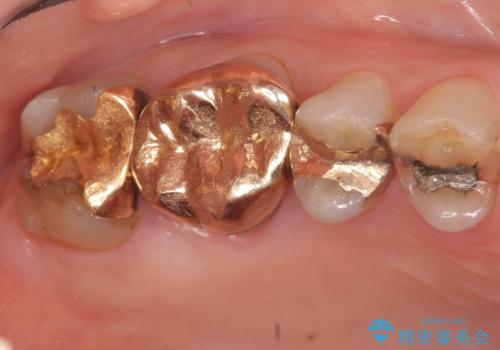

- 冷たいものがしみる右上の奥歯を治療して欲しいといらっしゃった方の症例です。

右上6,7の金歯を外したところ、虫歯が歯茎より深い位置まで進行していたため歯周外科を行いました。